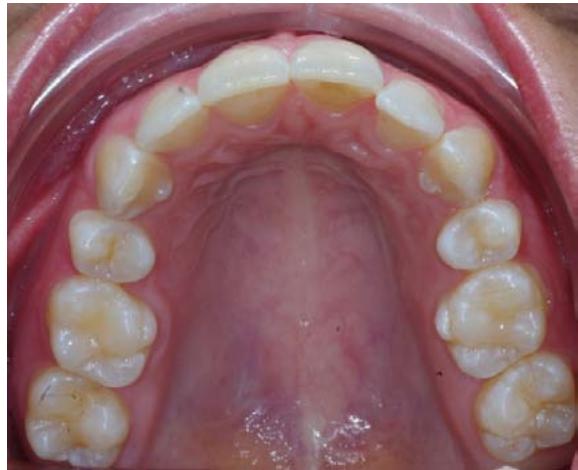

L'examen endobuccal montre une supraclusion incisive, une DDM et un sens transversal correct. Dans le sens sagittal, on note une classe Il dentaire.

Examen endobuccal